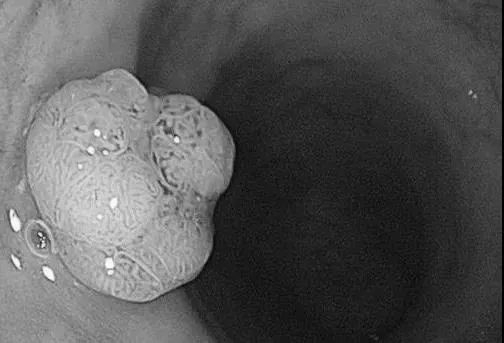

直肠管状腺瘤

而检查结果令人吃惊:14人全部发现息肉(全部是腺瘤),大肠癌的前身90%是肠息肉演变的,其中确诊直肠癌合并息肉1例。

很多人还不了解肠息肉,肠息肉大致上分为两类:一类叫做非肿瘤性息肉,一般不会癌变;另一类叫肿瘤性息肉,包括腺瘤性息肉、锯齿样病变、侧向发育性息肉、家族性息肉病等;这些息肉从理论上讲,只要时间足够,100%会癌变。